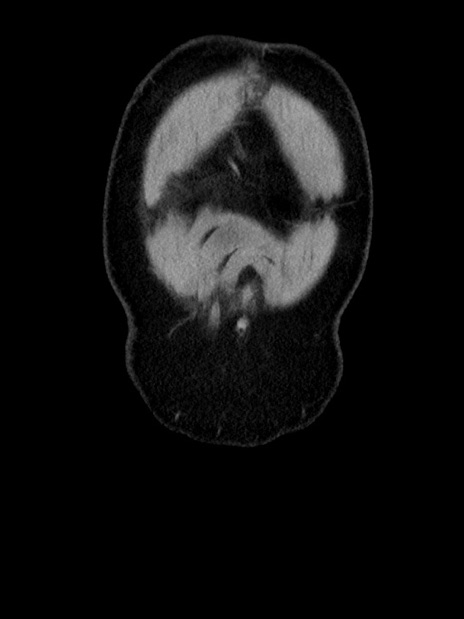

横断像

【症例】70歳代 男性

【主訴】腹部膨満、嘔吐

【現病歴】昨日より腹部膨満感出現。本日増悪し、仙痛出現。嘔吐あり、受診。

【既往歴】糖尿病、胆摘後

【身体所見】BP 149/80mmHg、HR 74/min、BT 35.9℃、腹部:膨満、軟、圧痛なし。腸雑音減弱あり。上腹部正中切開瘢痕あり。

【データ】WBC 13500、CRP 1.72